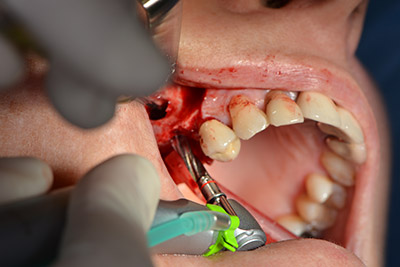

An absorbable membrane was used as the barrier in the buccal direction and covered the augmentation. Finally, saliva-proof sutures were placed (Fig. 15 to 19).

Augmentation with autologous bone

Image 15

Image 16

Implantation

Image 17

Implantology

Image 18

saliva-proof wound closure

Image 19